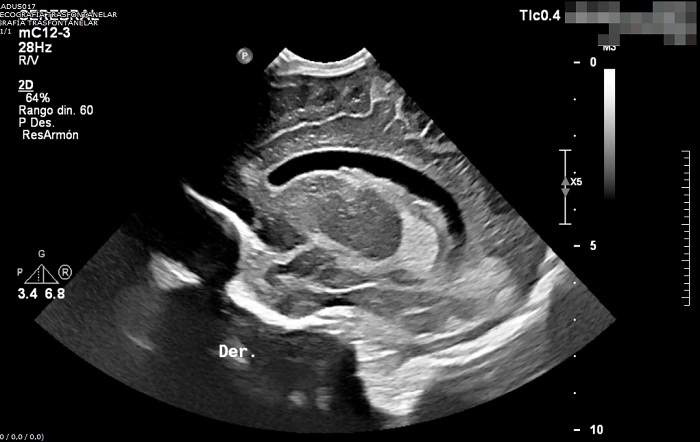

Ecografía transfontanelar. Hidrocefalia leve con prominencia e irregularidad de los plexos coroideos con posible ocupación de las astas occipitales de ventrículos laterales (de predominio derecho). Se sospecha la posibilidad diagnóstica de ventriculitis en paciente con diagnóstico de meningitis aguda.

No es posible analizar la ADA debido a interferencias por hemólisis. Debido a la alteración bioquímica en el LCR, se decide realizar ecografía transfontanelar, que muestra dilatación ventricular sugerente de ventriculitis.